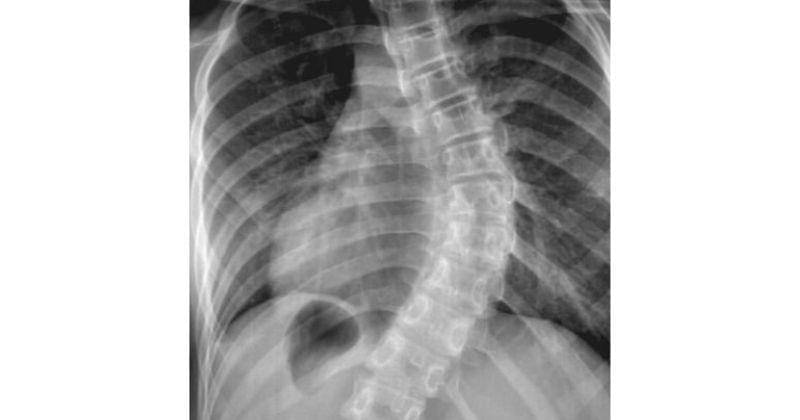

Namun, karena bayi belum bisa berdiri dengan sempurna, pemeriksaan skoliosis secara akurat dapat dilakukan dengan melalui tes x-ray.

Selanjutnya derajat kelengkungan tulang belakang dapat diukur setelah pemeriksaan x-ray.